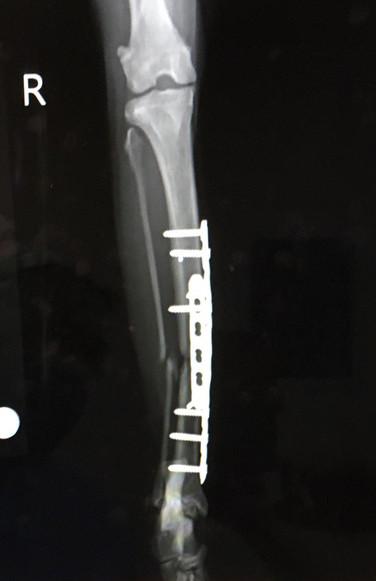

8月12日 手術から約2週間(17日)後

地元病院、バンテージ取る、消炎剤終了

8月16日 手術から3週間後

札幌病院、経過観察 エリザベスカラー終了